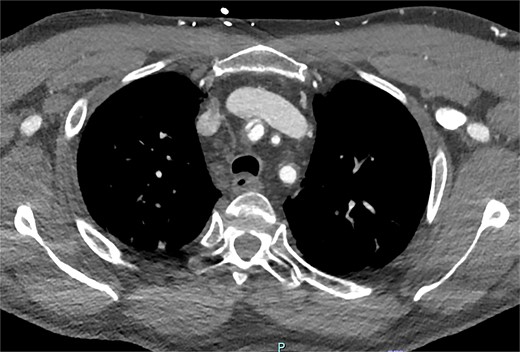

On arrive to the emergency department, the patient was found to be hypertensive with a blood pressure of 220/120 mmHg. Physical examination of the patient revealed no significant clinical findings. Serial troponins with corresponding ECG’s were undertaken which demonstrated no new evidence of myocardial ischaemia. Based upon the patient’s symptomatology, he underwent a CT aortogram which demonstrated a dissection arising from the proximal brachiocephalic artery. No dissection was noted in the ascending aorta, and there was no evidence of the brachiocephalic artery dissection extending into the subclavian or carotid arteries (Figs 1–3).

Coronal slice from CT aortogram demonstrating the origin of the dissection flap.